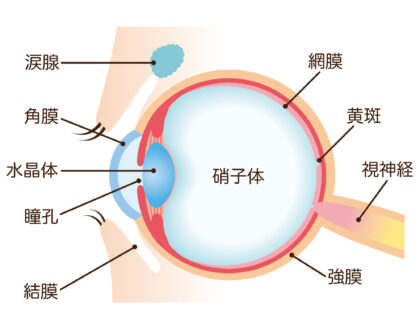

硝子体は眼球内を満たす無色透明のゲル状の組織です。角膜と水晶体から入ってきた光は硝子体を通って網膜で焦点を結びます。硝子体内には血管がありませんが、眼底で出血を起こすと硝子体内に血液が入り込む硝子体出血を起こすことがあります。

硝子体は眼球内を満たす無色透明のゲル状の組織です。角膜と水晶体から入ってきた光は硝子体を通って網膜で焦点を結びます。硝子体内には血管がありませんが、眼底で出血を起こすと硝子体内に血液が入り込む硝子体出血を起こすことがあります。